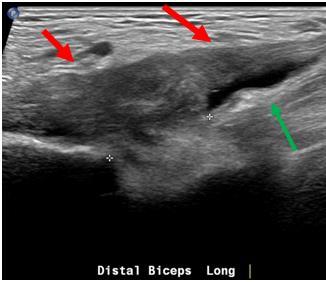

Fig. 4 Ultrasound showing biceps tendon retraction causing bunching and thickening of the torn tendon stump.

Fig. 2 Ultrasound showing normal biceps tendon (white arrows). Fig. 3 Ultrasound: The distal biceps tendon is ruptured. There is fluid and haematoma at the tendon defect (red arrow), and the tendon is retracted proximally (white arrow).

Fig. 8 Long section ultrasound image showing distal biceps tendinosis and bicipitoradial bursitis. The tendon is abnormally thickened and hypoechoic (red arrows) and there is fluid around the insertion in the bicipitoradial bursa (green arrow).